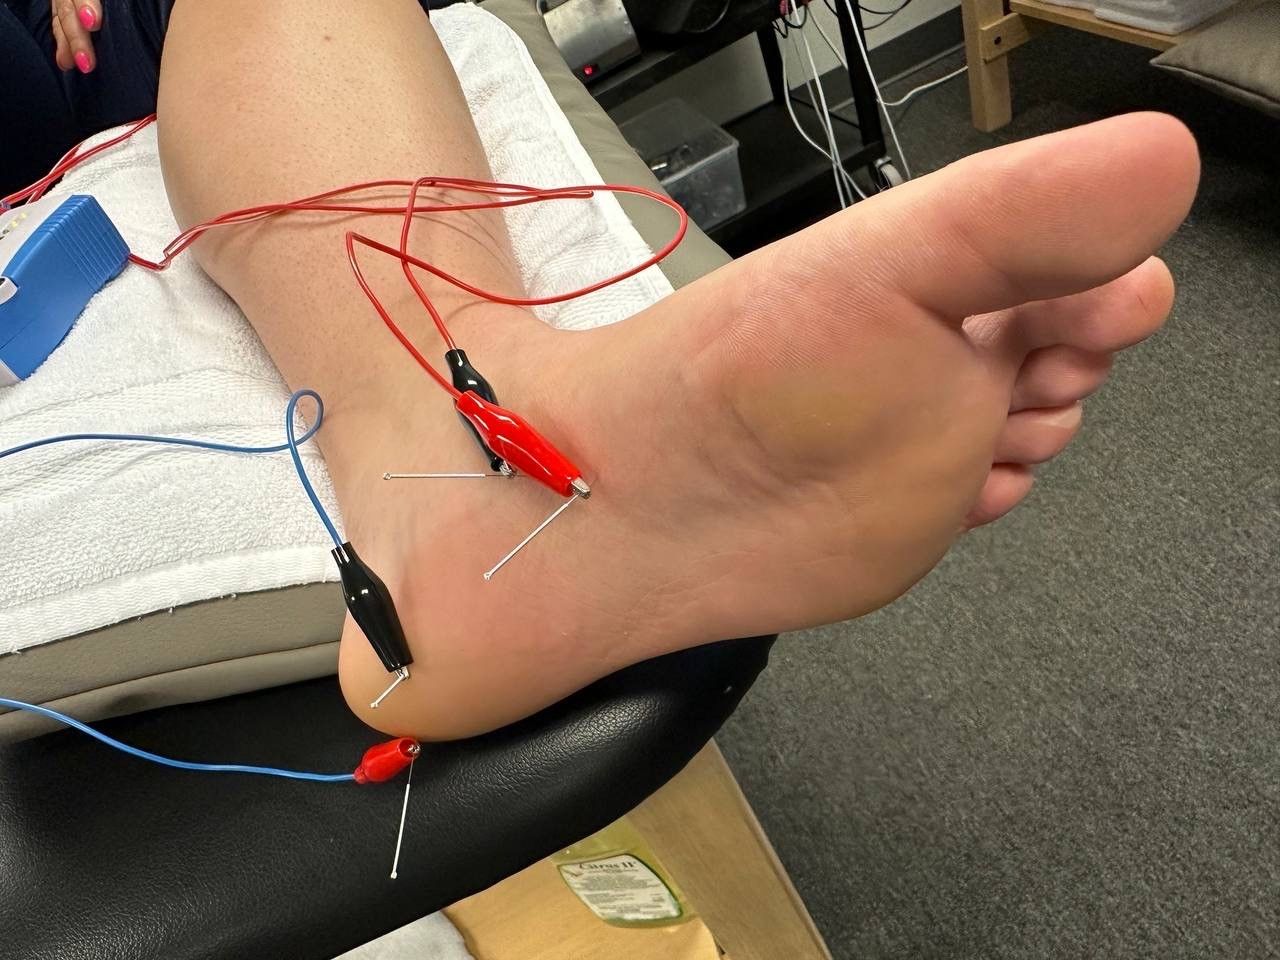

Dry needling calf plantar fasciitis outlet

Dry needling calf plantar fasciitis outlet, Dry Needling Therapy as a Potential Treatment Option for Plantar Fasciitis Podiatry Today outlet

Dry needling calf plantar fasciitis outlet

Dry Needling Therapy as a Potential Treatment Option for Plantar Fasciitis Podiatry Today

Dry Needling Manipulation to Treat Cure Plantar Fasciitis Foot Pain Intricate Art Spine Body Solutions

Therafit Physical Therapy Dry Needling in Lowell MA

Trigger Point Dry Needling the Calf